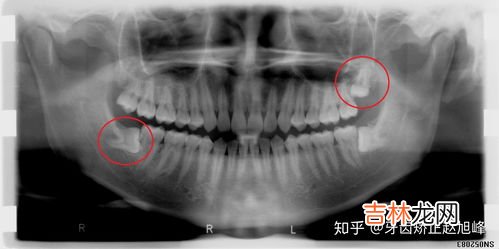

但如果你在嘴里没有看见智齿,并不意味着你就没有智齿,智齿也有可能是潜伏在牙床下边 。所以如果你嘴里只有28颗牙,也还不能确定有没有智齿,一般只有拍了 x 光才能确定智齿的情况 。

智齿的生长 , 具有很大的个体差异性,有的人20岁之前,有的人40、50岁才长,有的人终生不长,这都是正常的 。通常四颗智齿不会全部长全,有的人只长1~2颗,有的智齿长到一半就不再生长 。长到一半就不再生长的智齿,称为阻生智齿 。阻生智齿一般是要拔除的 , 因为其危害性比较大 。